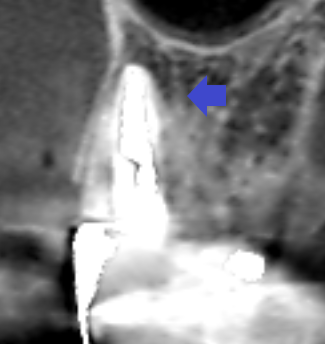

ブリッジの支台になっている上顎側切歯に大きな膿がみられ、この歯を残せなければ無傷の隣の犬歯を削ってブリッジの支台にしなければいけないケースです。できれば、上顎側切歯の膿を治して再度ブリッジの支台として使いたいので、精密再根管治療を行うことになりました。 上顎側切歯の冠状断のCT画像です。 側切歯の根…